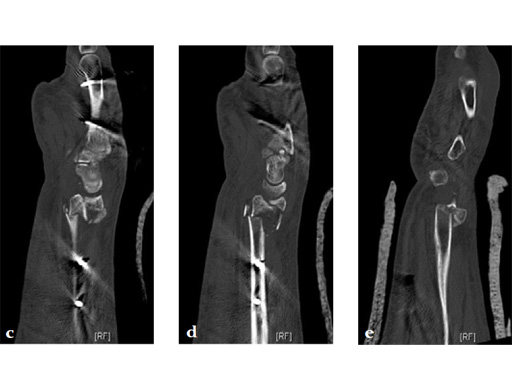

Fig 3ce Radius with hyperextended palmar-ulnar key fragment.